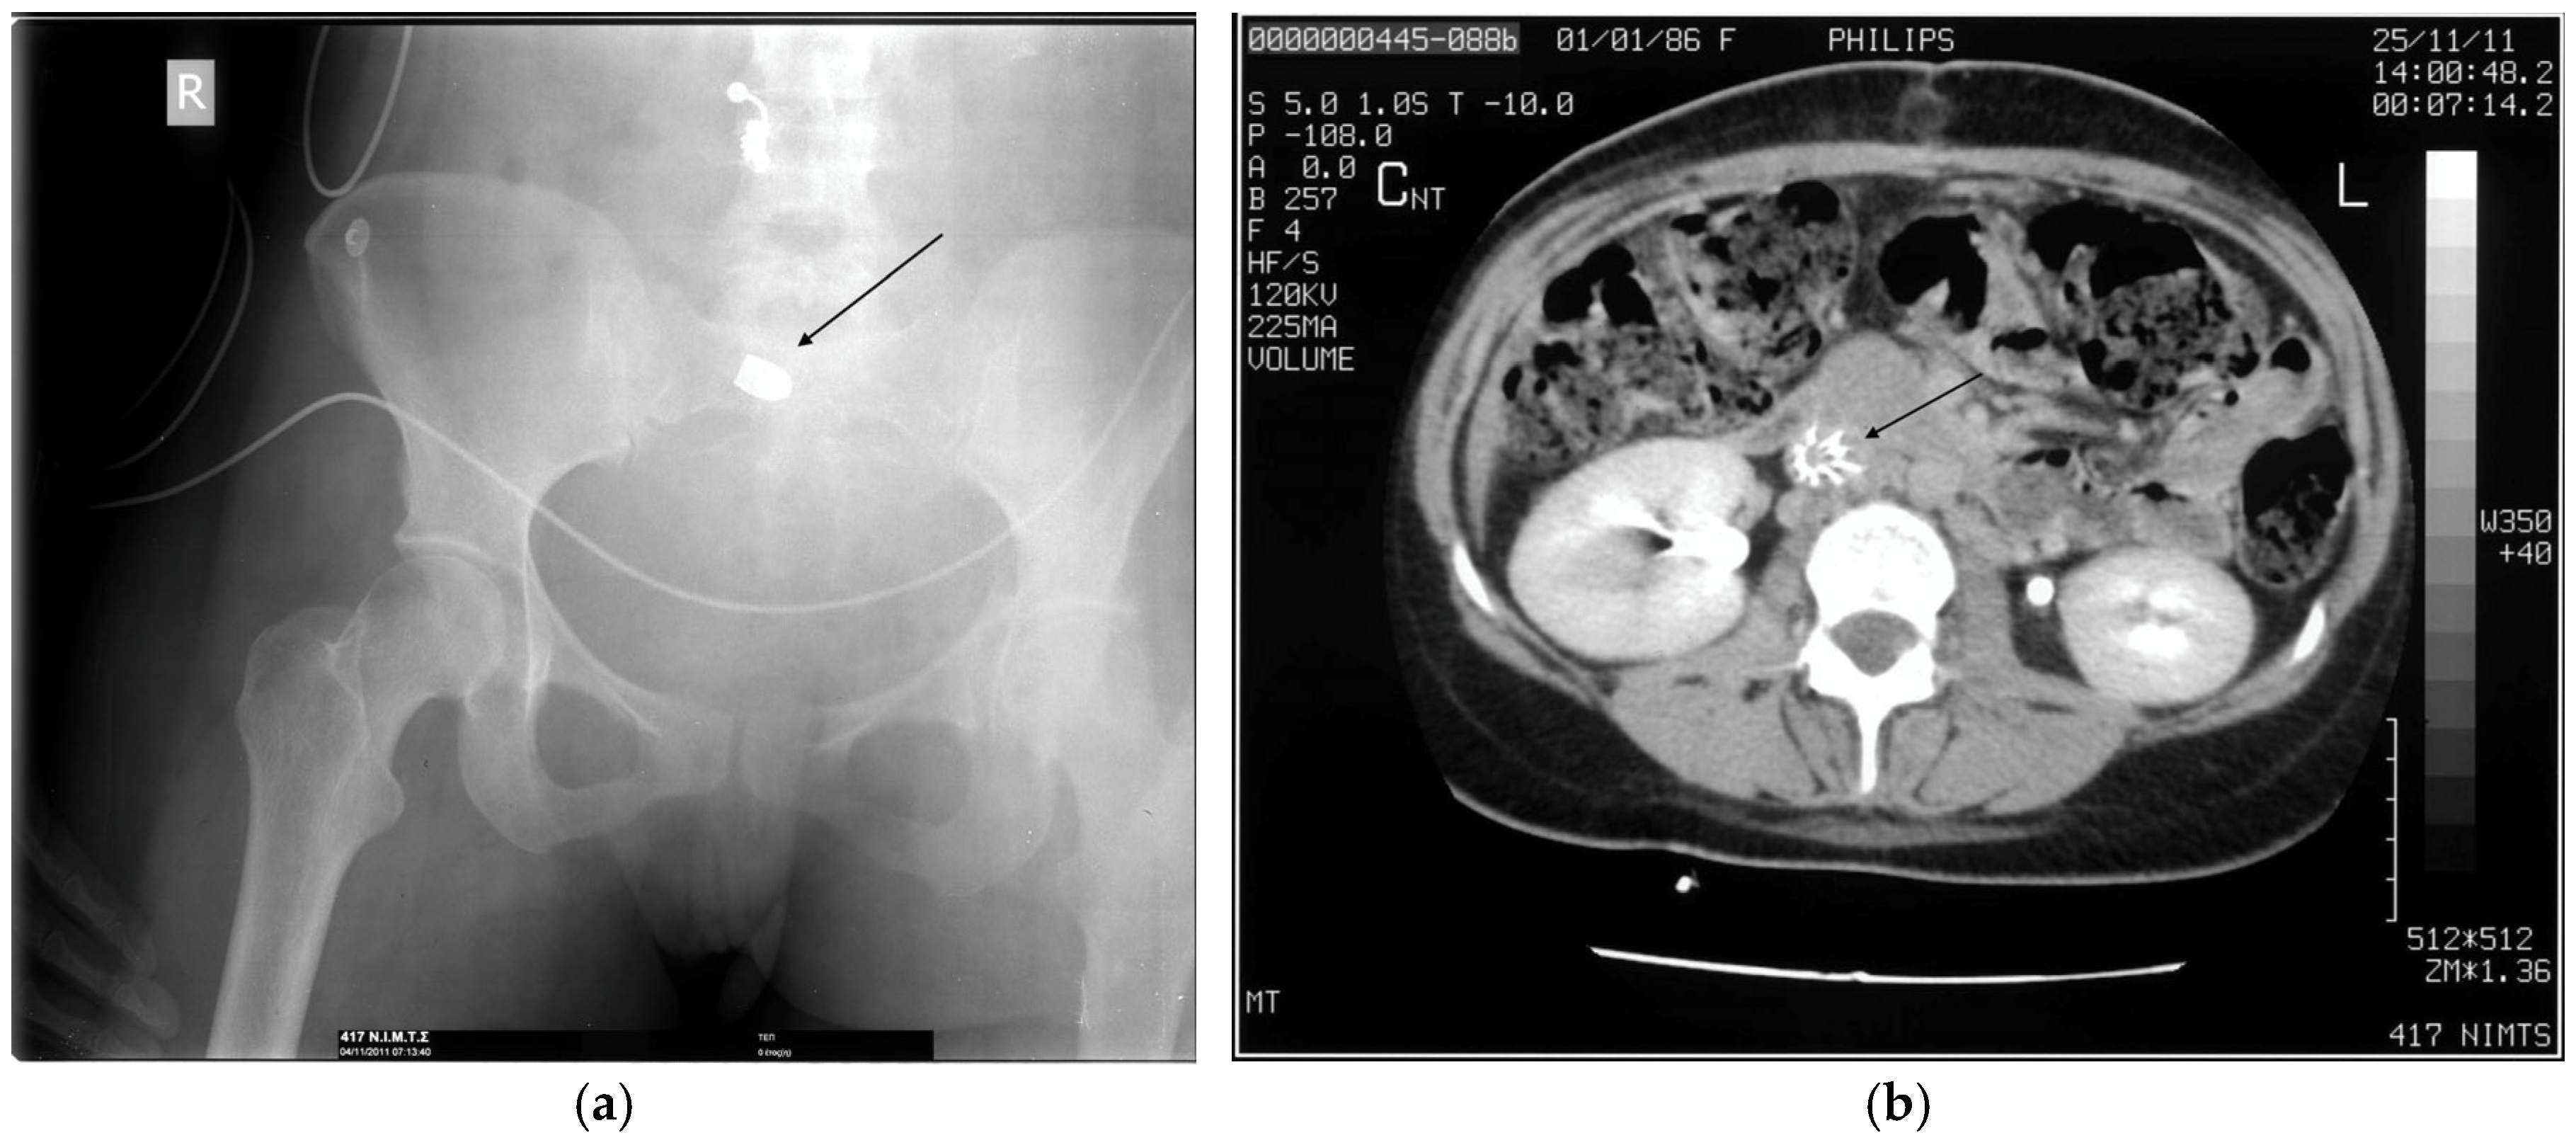

- Serafetinides, E.S. Renal and ureteric trauma. In Primer on Urology; Chapple, C.R., Wein, A.J., Eds.; Springer: Cham, Switzerland, 2025; pp. 1013–1024. [Google Scholar] [CrossRef]

- Karademir, K.; Gunhan, M.; Can, C. Effects of blast injury on kidneys in abdominal gunshot wounds. Urology 2006, 68, 1160–1163. [Google Scholar] [CrossRef]

- Naeem, M.; Hoegger, M.J.; Petraglia, F.W.; Ballard, D.H.; Zulfigar, M.; Patlas, M.N.; Raptis, C.; Mellnick, V.M. CT of penetrating abdominopelvic trauma. Radiographics 2021, 41, 1064–1081. [Google Scholar] [CrossRef]